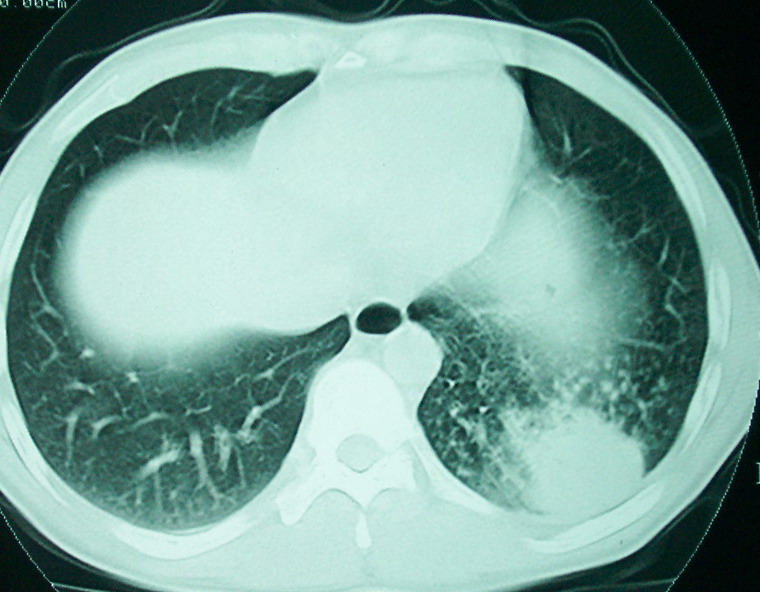

m      37y      发热   咳脓痰月余      ct肺脓肿但住院抗炎治疗后双肺内结节不知该如何解释

治疗后见左肺下野病灶较前缩小但双肺内结节影似无变化请较各位老师该如何下结论    治疗前wbc14.5 治疗后wbc 11.0

左下叶肺癌,双肺转移

我看是不是可以两元化来解释,左肺下叶还是肺脓疡,而其余病灶考虑肺癌伴肺内转移,我看右肺上叶尖段病灶可见明显毛刺改变为原发病灶.

1、左下肺鳞癌伴两肺及纵隔淋巴结转移;

左下肺病灶除了明显的厚壁空洞 气液平外,明显见壁结节,另两肺多发小结节,综合考虑:左下肺周围性肺癌伴肺内转移.

如果你仔细的同层面对比,你会发现所有的病灶均有比较明显的吸收、缩小。病变的形态,特别是脓肿的形态、壁的厚薄、内壁均有很大的变化,均在往好的方面发展。与临床症状、血像均符合,治疗效果比较显著,就是肺脓肿并双肺的化脓性炎症灶。